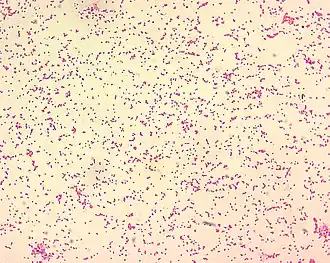

Morphologie

Brucella est un très petit coccobacille à Gram négatif de 0,5-0,7 x 0,6-1,5 µm (7,5 µm pour un globule rouge). La bactérie est immobile, non encapsulée, non sporulée, aérobie stricte et intra-cellulaire facultative.

Il en existe plusieurs espèces dont quatre sont pathogènes pour l’homme : principalement B. melitensis, B. abortus bovis, B. suis et accessoirement B. canis.